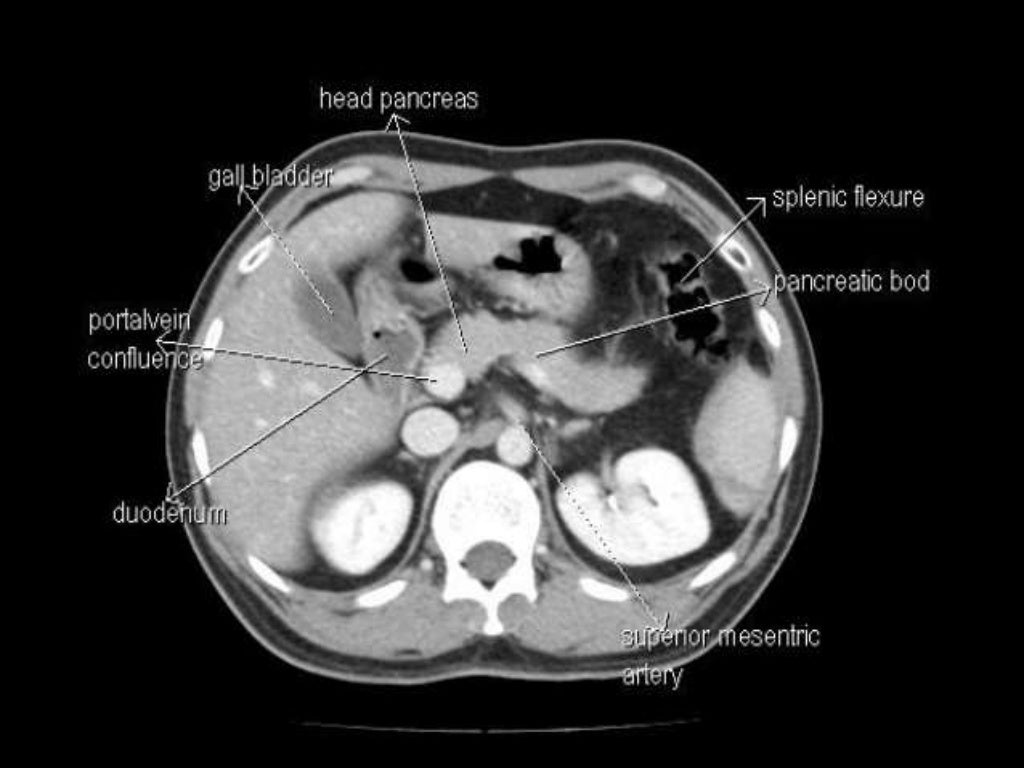

Anatomy ct abdomen

- Anatomy abdomen ct scan

- Sectional anatomy ct abdomen

- Normal anatomy ct abdomen

- Axial ct anatomy abdomen

- Abdomen anatomy ct radiopaedia

- Ct abdomen anatomy radiology

- Ct abdomen anatomy images

- Cross sectional anatomy ct abdomen